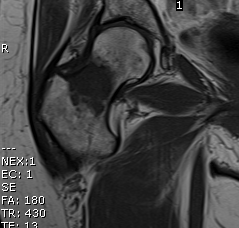

Distal Femur Fractures

1. Supracondylar

2. Unicondylar

3. Intracondylar

Supracondylar / Extra-condylar

1. Supracondylar

2. Unicondylar

3. Intracondylar

Supracondylar / Extra-condylar